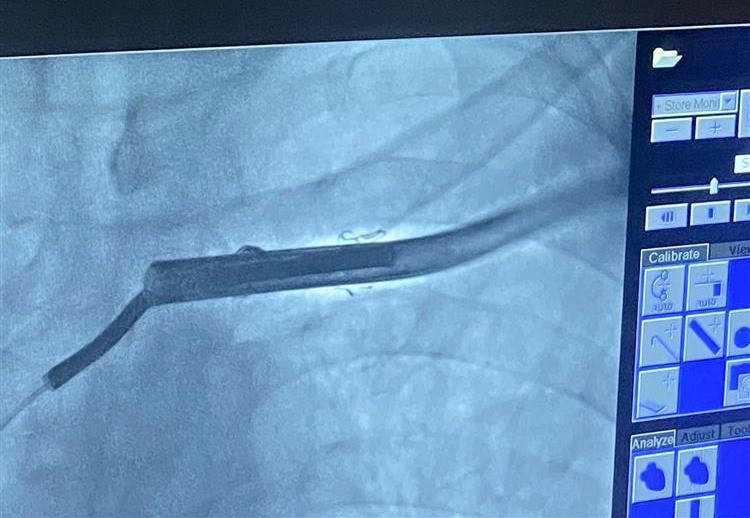

Yapılan pil kontrolünde verilen şokun uygunsuz olduğu, kablo ölçümlerinde kablonun kırık olduğu tespit edilmesi üzerine kablonun çıkarılması için hastanın yatışı yapıldı.

Hastane hekimi ve Artuklu Üniversitesi Tıp Fakültesi Kardiyoloji Ana Bilim Dalı Başkanı Prof. Dr. Mehmet Zülkif Karahan yönetimindeki ekip tarafından yaklaşık 2 saat süren başarılı operasyonla kablo, kalpten çıkarıldı.